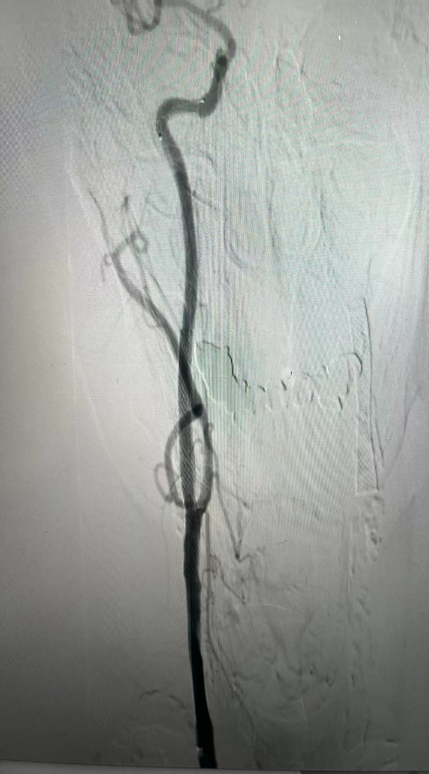

CASE 3:74岁女性,左侧颈动脉重度钙化狭窄,IVL治疗后管腔获得理想,支架置入后残余狭窄低。

左侧颈动脉

重度钙化狭窄

IVL后即刻管腔

获得理想

支架后

残余狭窄低